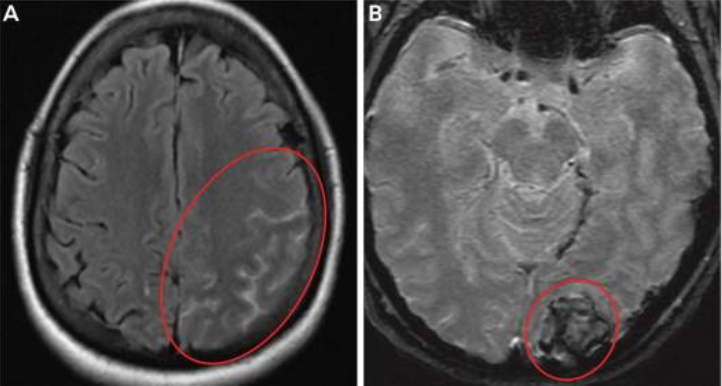

Reversible Cerebral Vasoconstriction Syndrome

The RCVS syndrome is characterized by segmental, multifocal, transient, nonvasculitic vasospasm of the medium and large-sized cerebral vessels, and it frequently manifests as recurrent thunderclap headaches without or with corresponding neurologic impairments.(39) The majority of times, RCVS is brought on by an orgasmic experience, a serotonergic or sympathomimetic substance (such as cocaine or antidepressants), or the postpartum period, which can account for up to 20 % of occurrences. Similar to PRES, although RCVS vasculopathy is inherently reversible, the sequelae may not be severe, and fulminant RCVS may cause ischemic stroke, ICH, and/or SAH, which can have life-altering effects.(40) Patients with preeclampsia are more likely to experience PRES and RCVS, and these two conditions frequently coexist. This could be because endothelial failure, inflammation, and sympathetic hyperactivity, which are all associated with preeclampsia, share a common pathogenesis (figure 2).(38)

Figure 2. Imaging of the patient with preeclampsia and RCVS.

A, MRI shows a diffuse left-sided convexity subarachnoid hemorrhage (circled).

B, shows a left occipital intracerebral hemorrhage (circled).(38)